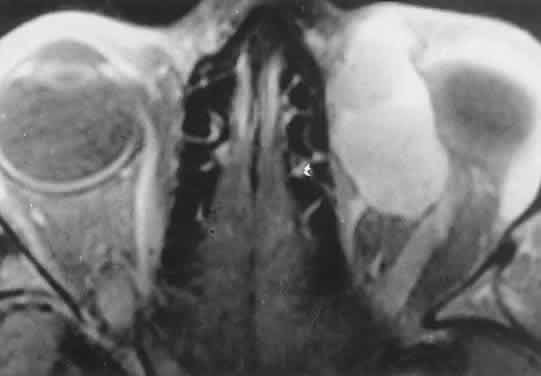

Within the orbit, rhabdomyosarcoma occurs most often, but not exclusively, in the superior nasal quadrant, with downward and outward displacement of the globe. CT scans show the topography of the orbital mass (Fig. 1A), as well as the possible extension into adjacent bone, paranasal sinuses, or the intracranial cavity. The circumscription that may be noted on CT is relative, because the lesion is not encapsulated and microscopically infiltrates normal tissue. Echography shows internal echoes of low-to-medium amplitude. Because the cellular tumor absorbs acoustic energy, the amplitude of the spikes falls off somewhat through the lesion (see Fig. 1B and C). MRI can help define the tumor's relationship to extraocular muscles (Fig. 2).

Fig. 2. MRI shows an intraconal tumor of lower intensity than the medial rectus muscle. The proximal muscle is splayed rather than compressed, suggesting that the lesion originated within the medial rectus. The diagnosis was alveolar rhabdomyosarcoma.